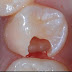

Kỹ thuật trám răng là gì?

Trám răng là kỹ thuật dùng những chất liệu đặc biệt để phục hồi chức năng nhai và thẩm mỹ cho răng. Vậy các phương pháp dùng để trám răng ...